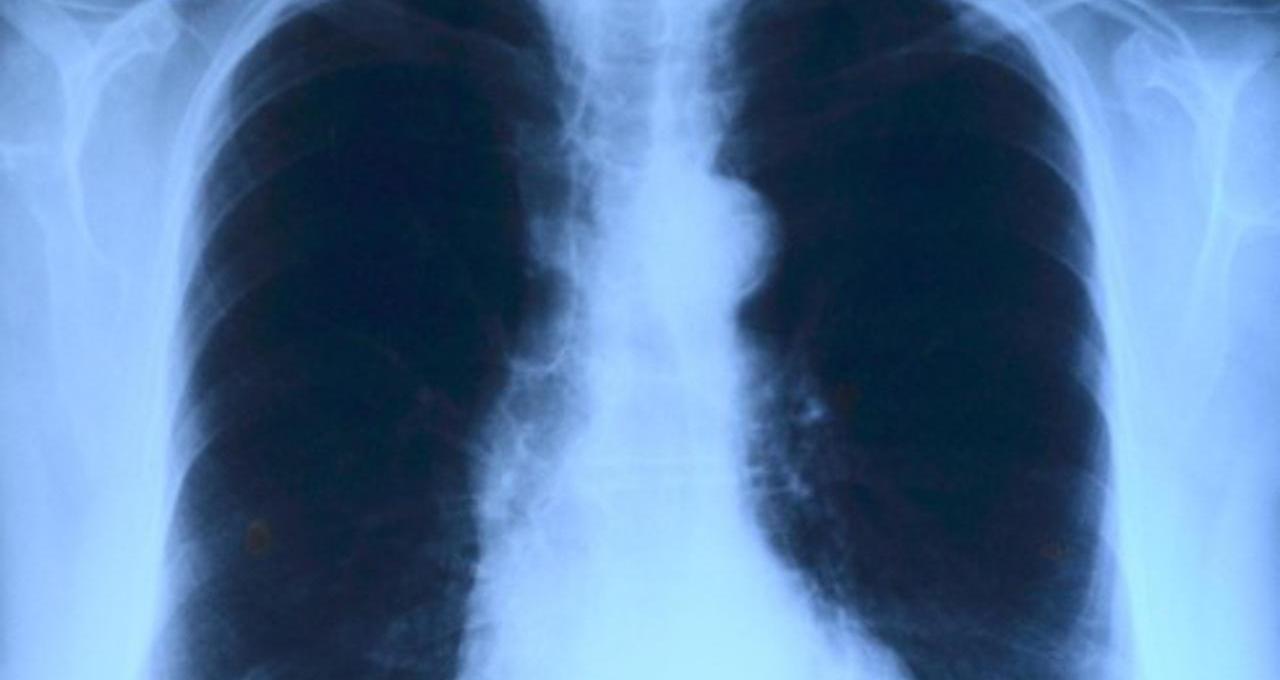

Poštar Paul Baxter (57) iz Prestona dugo je bolovao od jakog kašlja. Kao dugogodišnji pušač, pretpostavljao je da su tegobe povezane s njegovim životnim navikama. Situacija se pogoršala nakon upale pluća, kada je rendgenska snimka pokazala sumnjivu masu u plućima. Liječnici su u prvi trenutak pomislili da je riječ o tumoru.